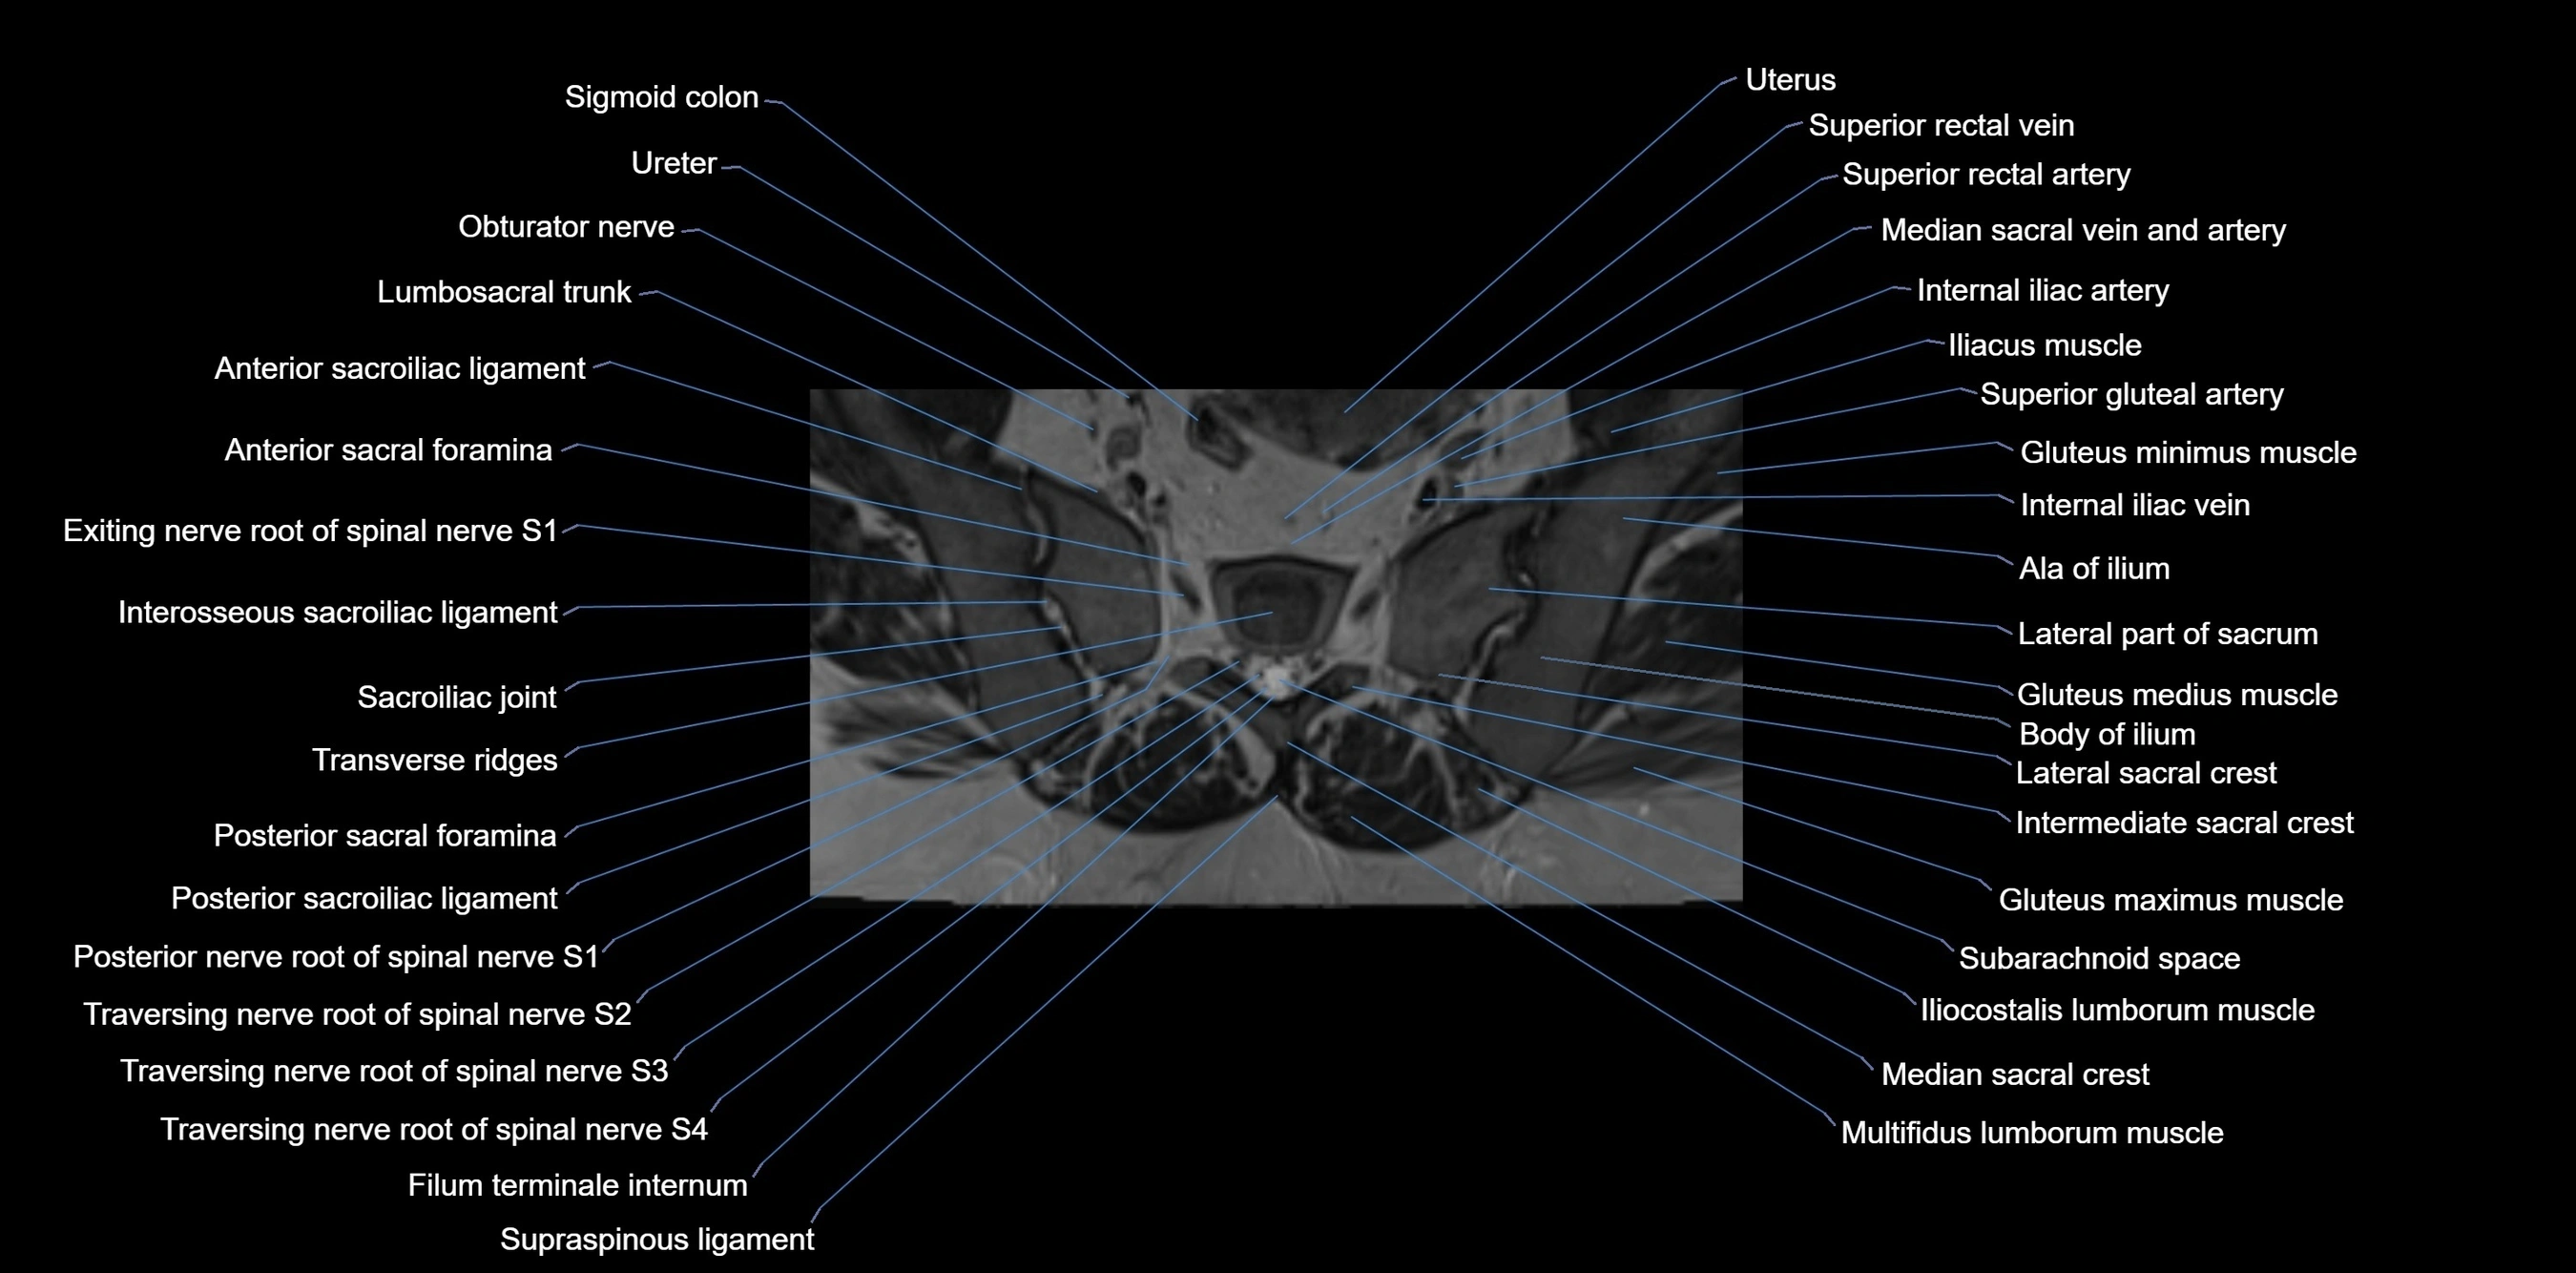

MRI image

image